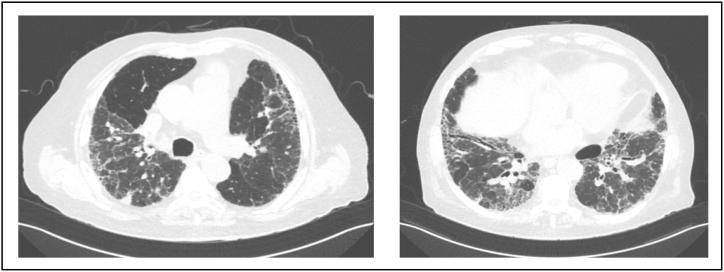

CASE 1: A 54-year-old woman from Honduras with known diagnosis of anti-MDA5 dermatomyositis presented for ILD. She denied respiratory symptoms. Computed tomography (CT) chest showed multifocal patchy areas of scattered groundglass opacities throughout all lobes of the lungs, predominately in a subpleural distribution within the lower lobes. Pulmonary function testing (PFTs) showed mild-to-moderate restriction. She was treated with mycophenolate mofetil monotherapy for her skin manifestations. At 18 months follow-up, she denied respiratory symptoms, and PFTs were normal.

病例1:一名来自洪都拉斯的54岁女性,已知患有抗MDA5皮肌炎,因间质性肺病前来就诊。她否认有呼吸道症状。胸部计算机断层扫描(CT)显示,肺部所有叶均有多发散在的斑片状磨玻璃影,主要分布在下叶的胸膜下区域。肺功能测试(PFTs)显示轻度至中度受限。她因皮肤表现接受霉酚酸酯单药治疗。在18个月的随访中,她否认有呼吸道症状,且肺功能测试结果正常。

病例2:一名来自古巴的80岁男性在肺部诊所就诊以建立治疗方案。他11年前被诊断为肺纤维化,抗MDA5阳性。他否认有呼吸道症状。肺功能测试显示中度阻塞和轻度至中度受限。胸部CT显示肺容积减小,结果符合普通间质性肺炎。他开始使用尼达尼布治疗。初次就诊15个月后,他的肺功能测试结果保持稳定。随访胸部CT显示肺纤维化稳定。在所有后续就诊中,他报告有轻度至中度、缓慢进展的劳力性呼吸困难,并继续使用尼达尼布治疗。在他最初被诊断为间质性肺病13年后,他被诊断出患有胰腺腺癌。